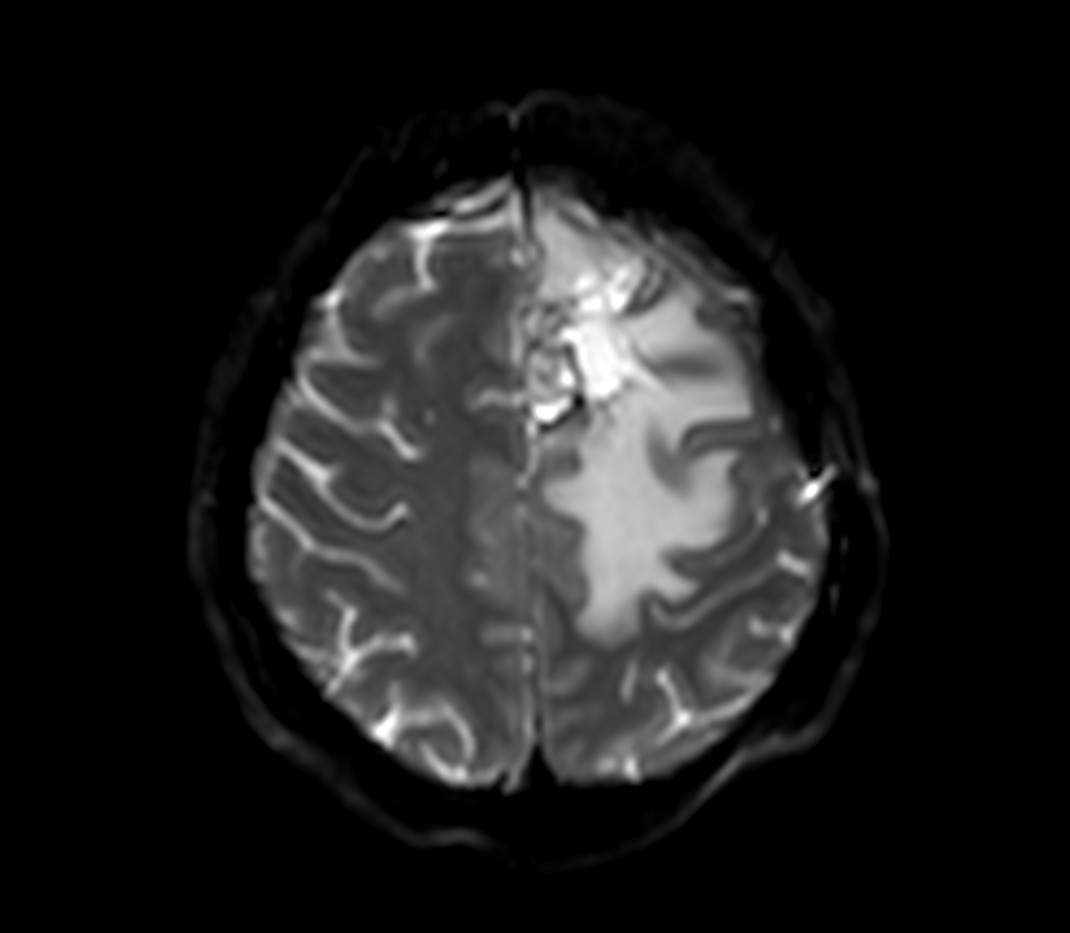

SmartSpeed Precise imaging for brain with glioblastoma

Kyushu University Hospital Japan